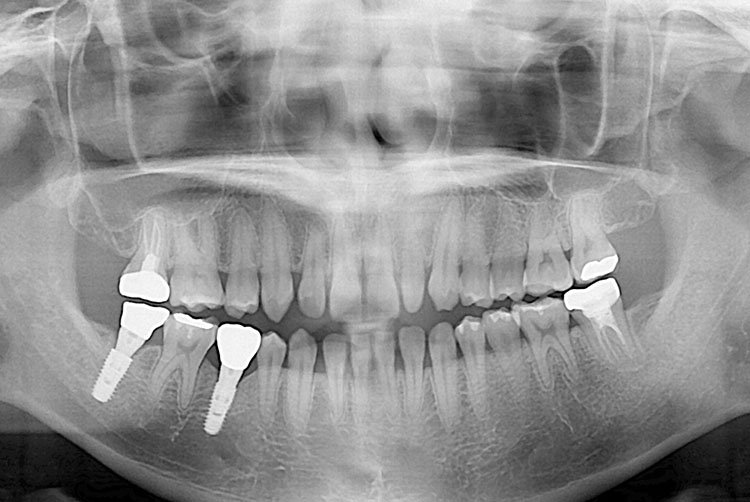

[임플란트] 임플란트

1fce06649d20a07a74e7e16677c05249.jpg

치료전 : 2015-05-27